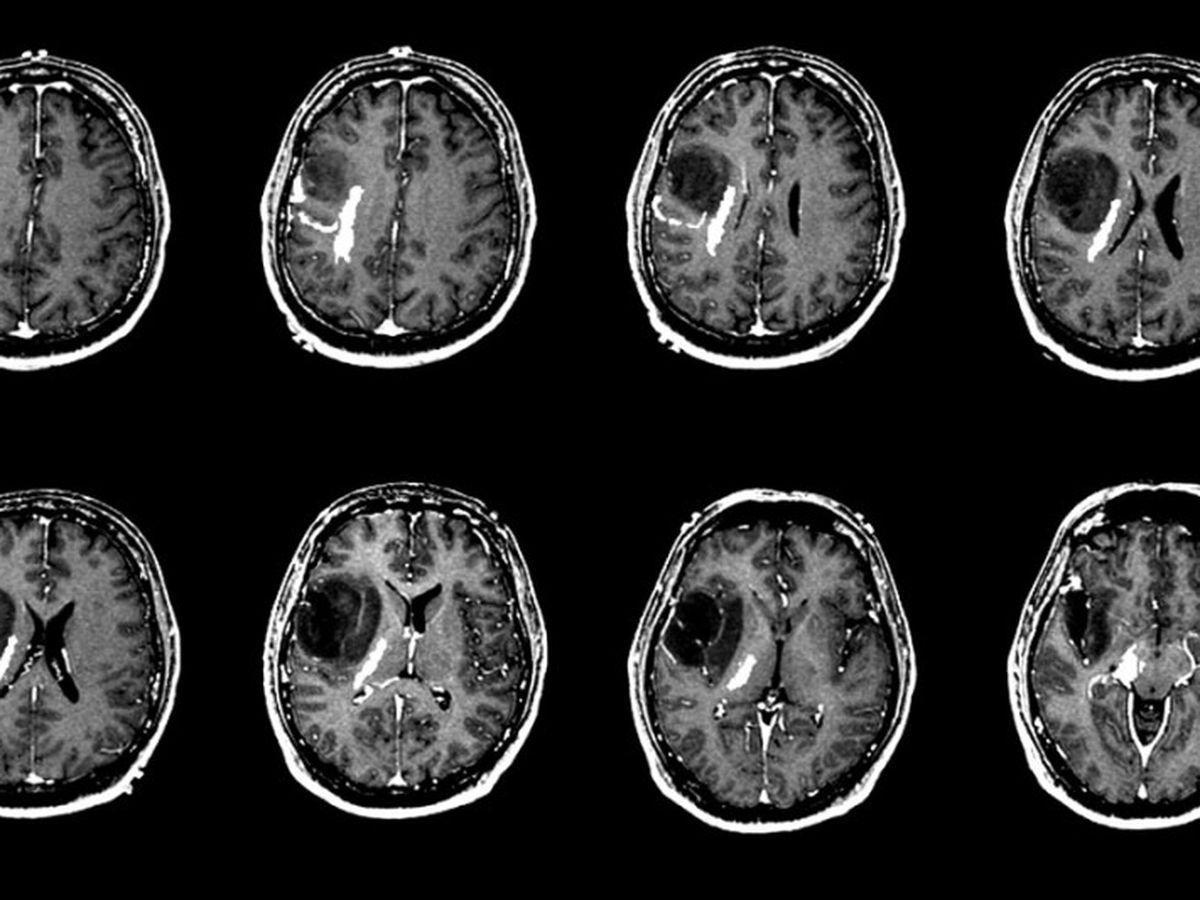

A very good friend of mine, a father of a large family, had severe headaches over last Shabbos (פרשת נשא) and went into Hospital early Sunday morning, after various tests and scans he was diagnosed with a growth in the brain and due to the extreme urgency of the situation he was operated on early Tuesday morning in Hadassah Hospital in ירושלים. The growth was ברוך השם benign (not cancerous) and was removed successfully.

He was released from hospital early this week, but due to the position of the growth his eyesight has been slightly affected and that may have a long term effect. The doctors are talking positively about returning to a normal life after a few months of rest but at the moment he is not allowed to work at all.